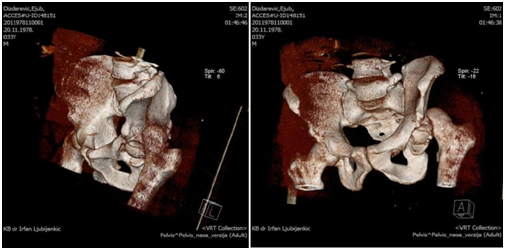

The patient at the age of 34 and 150kg of body weight suffered left hip posterior dislocation with femoral head fracture in car crash accident. The patient had been admitted to hospital after midnight. The mechanism of injury goes as follows: axial force and flexion in the hip caused by impact of the car. The left leg clinically observed is in painful extension, with minimal movement, strong pain and shortened leg. X-rays shows posterior hip joint dislocation and fracture of the femoral head. Closed reduction under anesthesia was unsuccessful. 3D CT reconstruction that had been taken before proceeding to open procedure shows posterior hip dislocation with femoral head fracture above fovea involving weight bearing portion- Pipkin type II fracture dislocation.

Preoperative x-rays, CT scans and 3D CT reconstructions in emergency department are presented as follows (Figure 1-5).

Figure 4 Preoperative 3D reconstructions.

Figure 5  Preoperative 3D reconstructions.